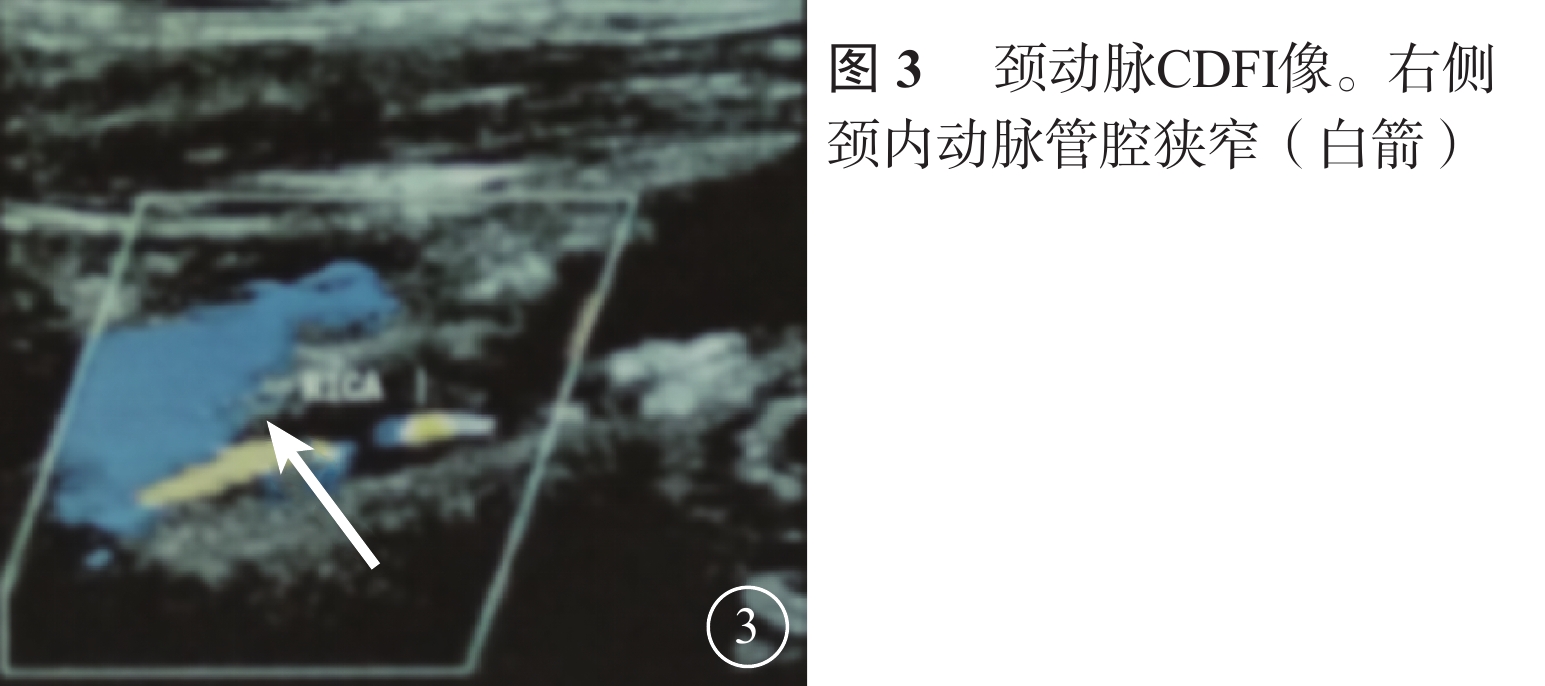

患者男,65歲。因右眼視物不見1周于2016年10月20日來我院就診。1周前無意中發現右眼視物不見,無眼紅、痛、畏光、流淚;自行使用芐達賴氨酸(商品名:莎普愛思)滴眼液滴眼無效而就診于外院。診斷為右眼新生血管性青光眼(NVG)?右眼視網膜病變(性質?);雙眼老年性白內障。既往高血壓病史8年,口服藥物治療。否認糖尿病、冠心病等其他全身病史。眼科檢查:右眼視力光感/眼前;左眼視力0.6,不能矯正。右眼眼壓17.3 mmHg(1 mmHg= 0.133 kPa),左眼眼壓12.7 mmHg。右眼前房深淺正常,周邊前房1 角膜厚度;瞳孔藥物性散大,邊緣全周可見虹膜新生血管(NVI),無后粘連;晶狀體混濁;玻璃體輕度混濁。眼底視盤邊界清楚,顏色橘紅,血管走形及比例基本正常;視網膜可見散在點片狀出血及片狀棉絨斑,黃斑中心凹反光不清(圖1)。左眼除晶狀體混濁、玻璃體輕度混濁,黃斑中心凹反光不清外,其余眼前節及眼底檢查未見明顯異常。熒光素眼底血管造影(FFA)檢查,右眼脈絡膜背景熒光充盈遲緩,視網膜動靜脈循環時間明顯延長(圖2)。光相干斷層掃描檢查,右眼后極部視網膜增厚,視網膜內層間反射信號大部分增強;左眼黃斑中心凹形態不規則。彩色超聲多普勒血流成像(CDFI)檢查,雙側頸總動脈、頸內動脈多發斑塊;右側頸內動脈管腔狹窄,約70%~99%(圖3)。頸動脈CT血管造影(CTA)檢查,顱內動脈硬化,可疑右側頸內動脈C1段重度狹窄;可疑兩側基底節區、右側丘腦腔隙性缺血灶。診斷:右眼眼缺血綜合征(OIS);雙眼老年性白內障;高血壓病。給予右眼玻璃體腔注射雷珠單抗0.05 ml治療。治療后3 d,視力數指/66 cm,眼壓15.0 mmHg;NVI完全消退。行右眼全視網膜激光光凝(PRP)治療。PRP治療后14 d檢查,右眼視力0.1;眼壓13.0 mmHg。轉血管外科行右側頸動脈內膜剝脫手術。手術后1個月復查,右眼視力0.4。FFA檢查,視網膜循環時間明顯改善(圖4)。

患者男,65歲。因右眼視物不見1周于2016年10月20日來我院就診。1周前無意中發現右眼視物不見,無眼紅、痛、畏光、流淚;自行使用芐達賴氨酸(商品名:莎普愛思)滴眼液滴眼無效而就診于外院。診斷為右眼新生血管性青光眼(NVG)?右眼視網膜病變(性質?);雙眼老年性白內障。既往高血壓病史8年,口服藥物治療。否認糖尿病、冠心病等其他全身病史。眼科檢查:右眼視力光感/眼前;左眼視力0.6,不能矯正。右眼眼壓17.3 mmHg(1 mmHg= 0.133 kPa),左眼眼壓12.7 mmHg。右眼前房深淺正常,周邊前房1 角膜厚度;瞳孔藥物性散大,邊緣全周可見虹膜新生血管(NVI),無后粘連;晶狀體混濁;玻璃體輕度混濁。眼底視盤邊界清楚,顏色橘紅,血管走形及比例基本正常;視網膜可見散在點片狀出血及片狀棉絨斑,黃斑中心凹反光不清(圖1)。左眼除晶狀體混濁、玻璃體輕度混濁,黃斑中心凹反光不清外,其余眼前節及眼底檢查未見明顯異常。熒光素眼底血管造影(FFA)檢查,右眼脈絡膜背景熒光充盈遲緩,視網膜動靜脈循環時間明顯延長(圖2)。光相干斷層掃描檢查,右眼后極部視網膜增厚,視網膜內層間反射信號大部分增強;左眼黃斑中心凹形態不規則。彩色超聲多普勒血流成像(CDFI)檢查,雙側頸總動脈、頸內動脈多發斑塊;右側頸內動脈管腔狹窄,約70%~99%(圖3)。頸動脈CT血管造影(CTA)檢查,顱內動脈硬化,可疑右側頸內動脈C1段重度狹窄;可疑兩側基底節區、右側丘腦腔隙性缺血灶。診斷:右眼眼缺血綜合征(OIS);雙眼老年性白內障;高血壓病。給予右眼玻璃體腔注射雷珠單抗0.05 ml治療。治療后3 d,視力數指/66 cm,眼壓15.0 mmHg;NVI完全消退。行右眼全視網膜激光光凝(PRP)治療。PRP治療后14 d檢查,右眼視力0.1;眼壓13.0 mmHg。轉血管外科行右側頸動脈內膜剝脫手術。手術后1個月復查,右眼視力0.4。FFA檢查,視網膜循環時間明顯改善(圖4)。